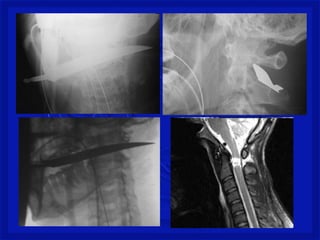

Medular Penetrante

•Perfuração da coluna (arma branca, tiro

ou estilhaço de bomba na coluna)

•Lesão medular completa ou incompleta,

associada ou não a lesão dos nervos

espinhais e/ou tronco dos plexos

nervosos.

•Quadro neurológico é variável.

Mecanismo de TraumaRaqui- Medular Penetrante •Perfuração da coluna (arma branca, tiro ou estilhaço de bomba na coluna) •Lesão medular completa ou incompleta, associada ou não a lesão dos nervos espinhais e/ou tronco dos plexos nervosos. •Quadro neurológico é variável.